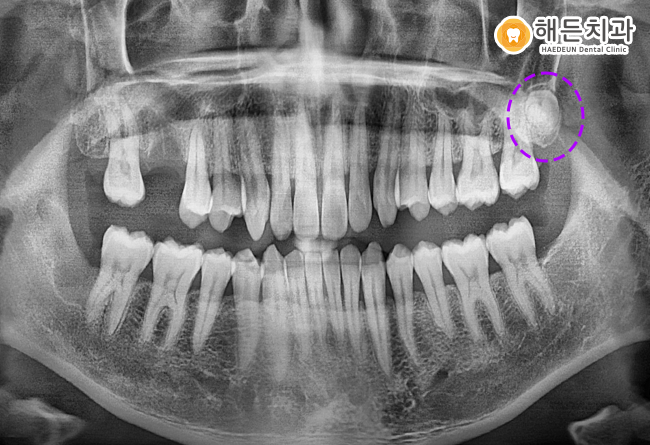

사랑니 2개와 뿌리만 남아있는 치아, 총 3개의 치아가 뿌리 끝까지 깨끗하게 발치된 모습을 확인하실 수 있습니다.

아직 왼쪽 위의 사랑니는 잇몸 위로 맹출되지 않았으며,

환.자분께서 느끼는 불편감이 없는 상태라 추후 뽑으시기로 하셨답니다.

더불어 치아뿌리만 남아있어 발치한 잔존치근의 부위에는, 상실된 부위를 대체해주는 치료가 필요함을 설명드렸습니다.

임플란트, 브릿지 등의 치료를 통해 자연치의 기능을 회복해주는 치료가 필요하답니다.